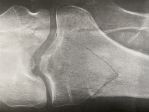

Bad is relative i suppose biggrin

Attachments

My God, John, you could open up a hardware store with all of those metal parts!